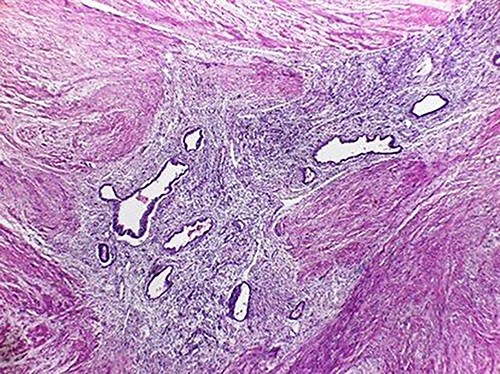

The microscopic study reported ileocolic intussusception and cecal endometriosis (Figs 4 and 5).

High magnification image (40x); endometrial gland and stroma without atypia. Erythrocytes within the lumen of the gland.